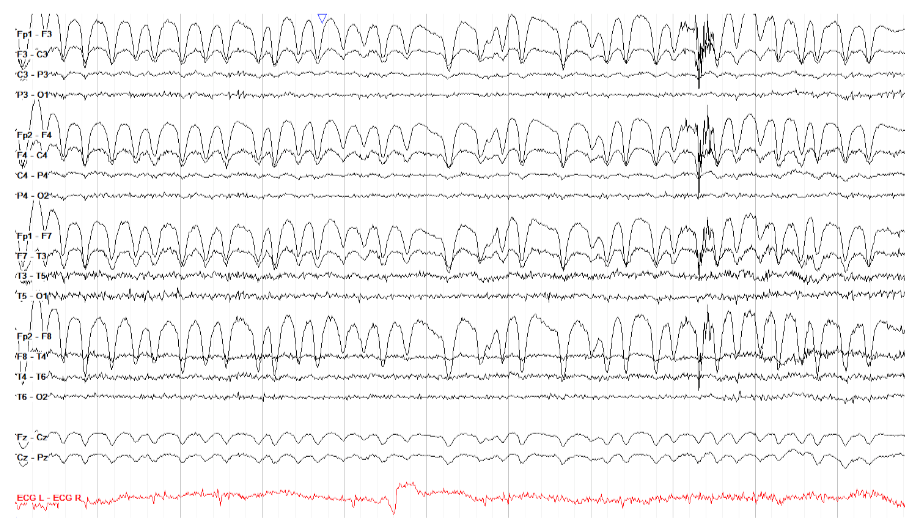

舌下伪影经常但不一定与咀嚼伪影一起出现。它由舌头的运动引起,并表现为较慢的、弥漫性的德尔塔频率活动。

注意,在下面的示例中,所有描记都具有本质上相同的运动——对于慢波睡眠之类的东西来说,这很有组织性,虽然发作模式肯定会导致这种节奏,但在这一页上没有证据表明癫痫发作特征随时间或地点的演变。

关于舌头运动伪影的一个值得注意的点是它是可重复的——你可以要求患者移动舌头,或者说“la la la”(又名舌音素),看看脑电图上是否显示出相同的模式。